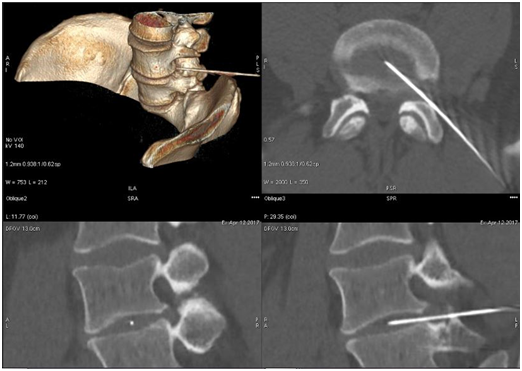

Technique of periradicular injection under CT control with laser navigation

The position of the patient and the preparation of the needle path is the same like in the case of ozone discolysis with the difference that now the target of the needle is the intervertebral foramen. After contact of the needle with the root, the patient usually signals this fact very clearly, however, in cases of intensified proliferative degenerative changes, the position of the needle must be confirmed by the control scan and 3D reconstruction. Then after aspiration a mixture of steroid and local anesthetics is administered slowly, observing the patient's condition, and after a while a mixture of ozone gas in a volume of 10-20ml is delivered depending on the patient’s tolerance. The patient should be informed about the temporary loss of motor function and the possibility of a temporary increase in the discomfort due to the volume effect (gas pressure). For the sake of safety after 2-6 hours of observation, the patient always leaves the clinic accompanied by family members. Check-up visit is usually set after 2-3 weeks. In case of a clear improvement, it is possible to continue the treatment with ACS to maintain the anti-inflammatory effect (Figure 3).

Figure 3 Periradicular injections under CT control with laser navigation of the L5S1 level.